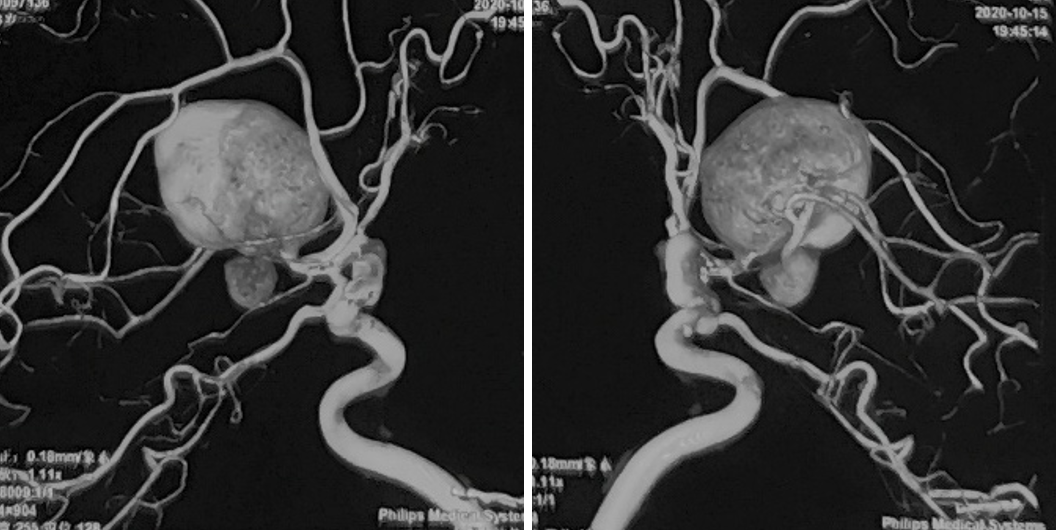

性别:女性,年龄:33 y.o

术前诊断: